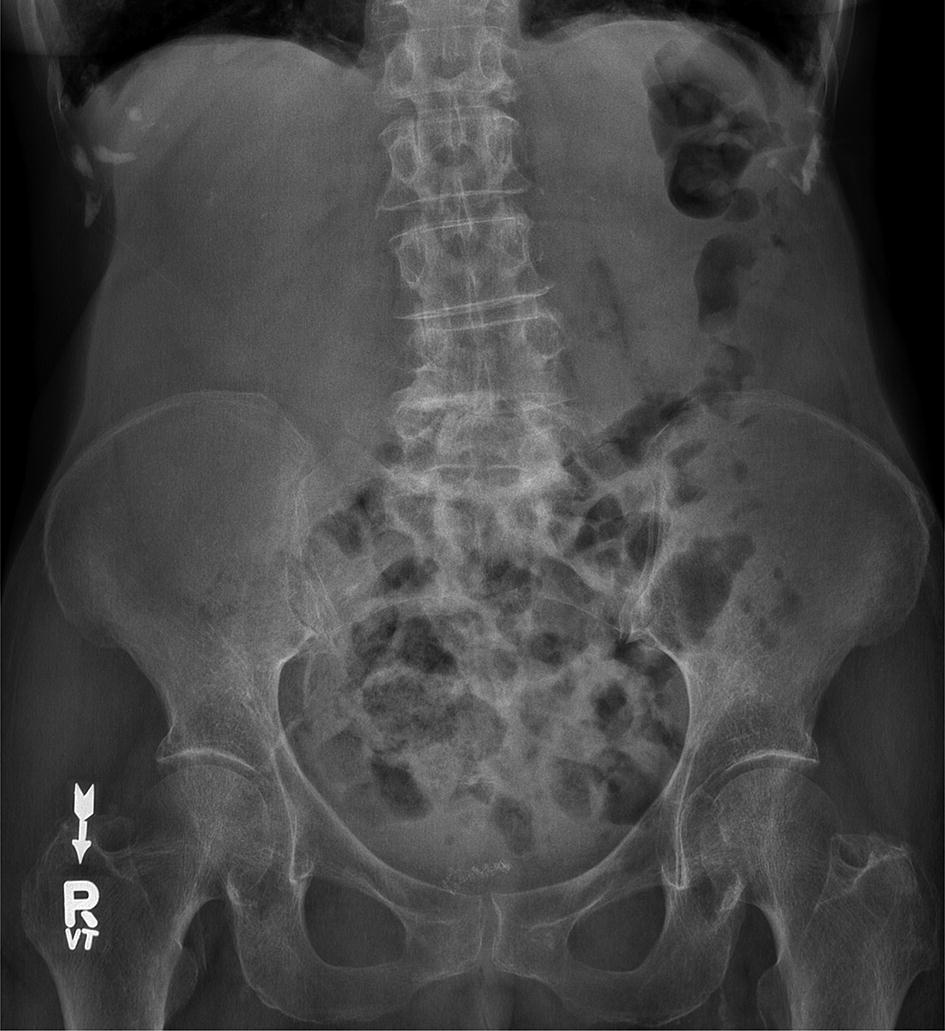

But as you can see from the images above you cannot reliably look for air under the diaphragm in an AXR and thus a CXR is. Typical abdominal X-ray features of small bowel obstruction include dilation of the small bowel 3cm diameter and much more prominent valvulae conniventes creating a coiled-spring appearance. Adhesions are the most common cause of small bowel obstruction in the developed world accounting for 75 of all cases. It integrated radiological images including X-ray computed tomography and magnetic resonance imaging plus clinical correlations and self-evaluation. Whether x-ray is supine or erect for fluid and gas levels correct orientation RightLeft Location of bowel small central large peripheral. A US doctor answered Learn more.

Approach to AXR Bowel gas pattern Extraluminal air Soft tissue masses Calcifications 4. This tutorial will discuss these steps. X-rays of the belly may be done to check the area for causes of abdominal pain. Typical abdominal X-ray features of small bowel obstruction include dilation of the small bowel 3cm diameter and much more prominent valvulae conniventes creating a coiled-spring appearance. Abdominal X-Ray - Small bowel obstruction - Small bowel obstruction can be identified by the dilated loops of centrally placed bowel with the venae commitantes circular bands of muscle that span the entire width of the bowel.

Abdominal X-Ray - Small bowel obstruction - Small bowel obstruction can be identified by the dilated loops of centrally placed bowel with the venae commitantes circular bands of muscle that span the entire width of the bowel. REM is the term. Because of the difference in X-ray absorption by air and soft tissues the intestinal structures intestinal air can be differentiated from their surroundings. It can also be done to find an object that has been swallowed or to look for a. Send thanks to the doctor.